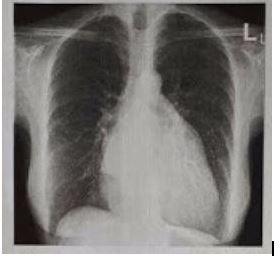

Paciente do gênero feminino, 65 anos, tabagista, hipertensa, apresenta dispneia de esforço e ortopneia de evolução progressiva. Realizada ausculta cardíaca com presença de sopro holossistólico, mais audível em região de ápice. O raio-X simples de tórax em PA (póstero-anterior) mostra a imagem abaixo. Adicionalmente à ecografia com Doppler, nota-se jato de alta velocidade de fluxo sanguíneo regurgitante para dentro do átrio esquerdo durante a sístole.